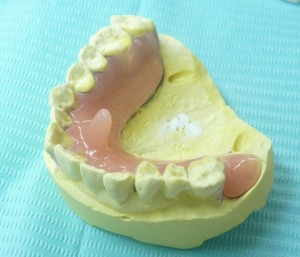

(2019/4/1追加) 最近のTPC 突起が長くなってきました

↑ わかりやすくするために色を塗っています ↑